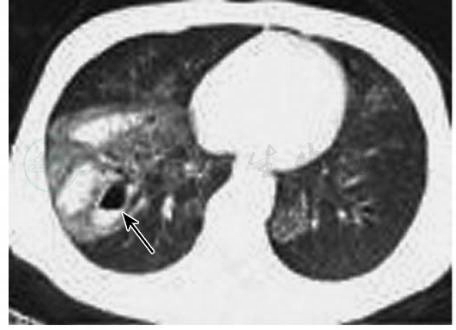

图4肺挫裂伤(磨玻璃气囊征)

男性,2岁,胸部CT平扫肺窗(A)显示右肺上叶斑片状高密度影及气体密度影,壁较厚,内可见多处分隔(箭);同层纵隔窗(B)显示右肺上叶含气囊腔的壁光滑,厚薄均匀

引自:中华影像医学·呼吸系统卷.第3版.ISBN:978-7-117-28903-0.主编:

图5肺挫裂伤(磨玻璃结节征)

男性,23岁,胸部CT平扫肺窗(A)显示右肺下叶片状磨玻璃样高密度影,内见结节状高密度影(箭),边界清晰,同层纵隔窗(B)显示右肺下叶结节密度均匀,轮廓光滑

图6肺挫裂伤(“磨玻璃气-液平囊腔征”)

男性,24岁,胸部CT平扫肺窗显示右肺下叶片状磨玻璃样高密度影,内见多发结节状高密度影,部分内见“气-液平面”(箭)